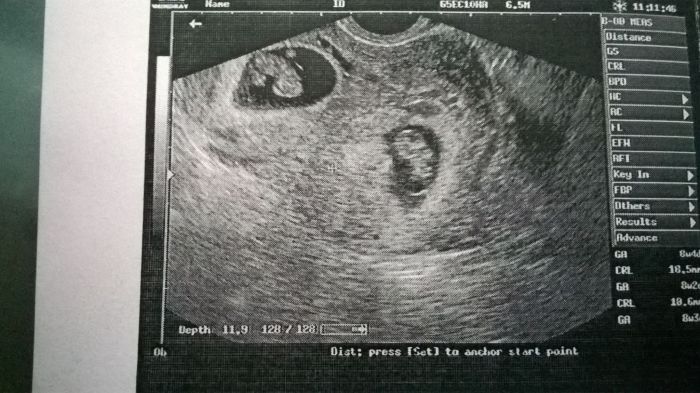

když mi dělala ultrazvuk, tak nevěřila vlastním očím, mám tam dvě miminka

když jsem to viděla, tak se ptám: a jsou obě živý??

takže syndrom mizejícího dvojčete nebyla správná diagnóza

prý ještě nemusel být vidět v 6 týdnu, když jsem byla na pohotovosti, protože ten jeden je vidět hůř, ale je tam, srdíčko mají obě, odpovídají stáří 8+4 a vypadají krásně živě

odcházela jsem v rozpoložené náladě, furt se v duchu smála

když jsem to ukázala manželovi, tak se taky začal smát

přikládám fotečku